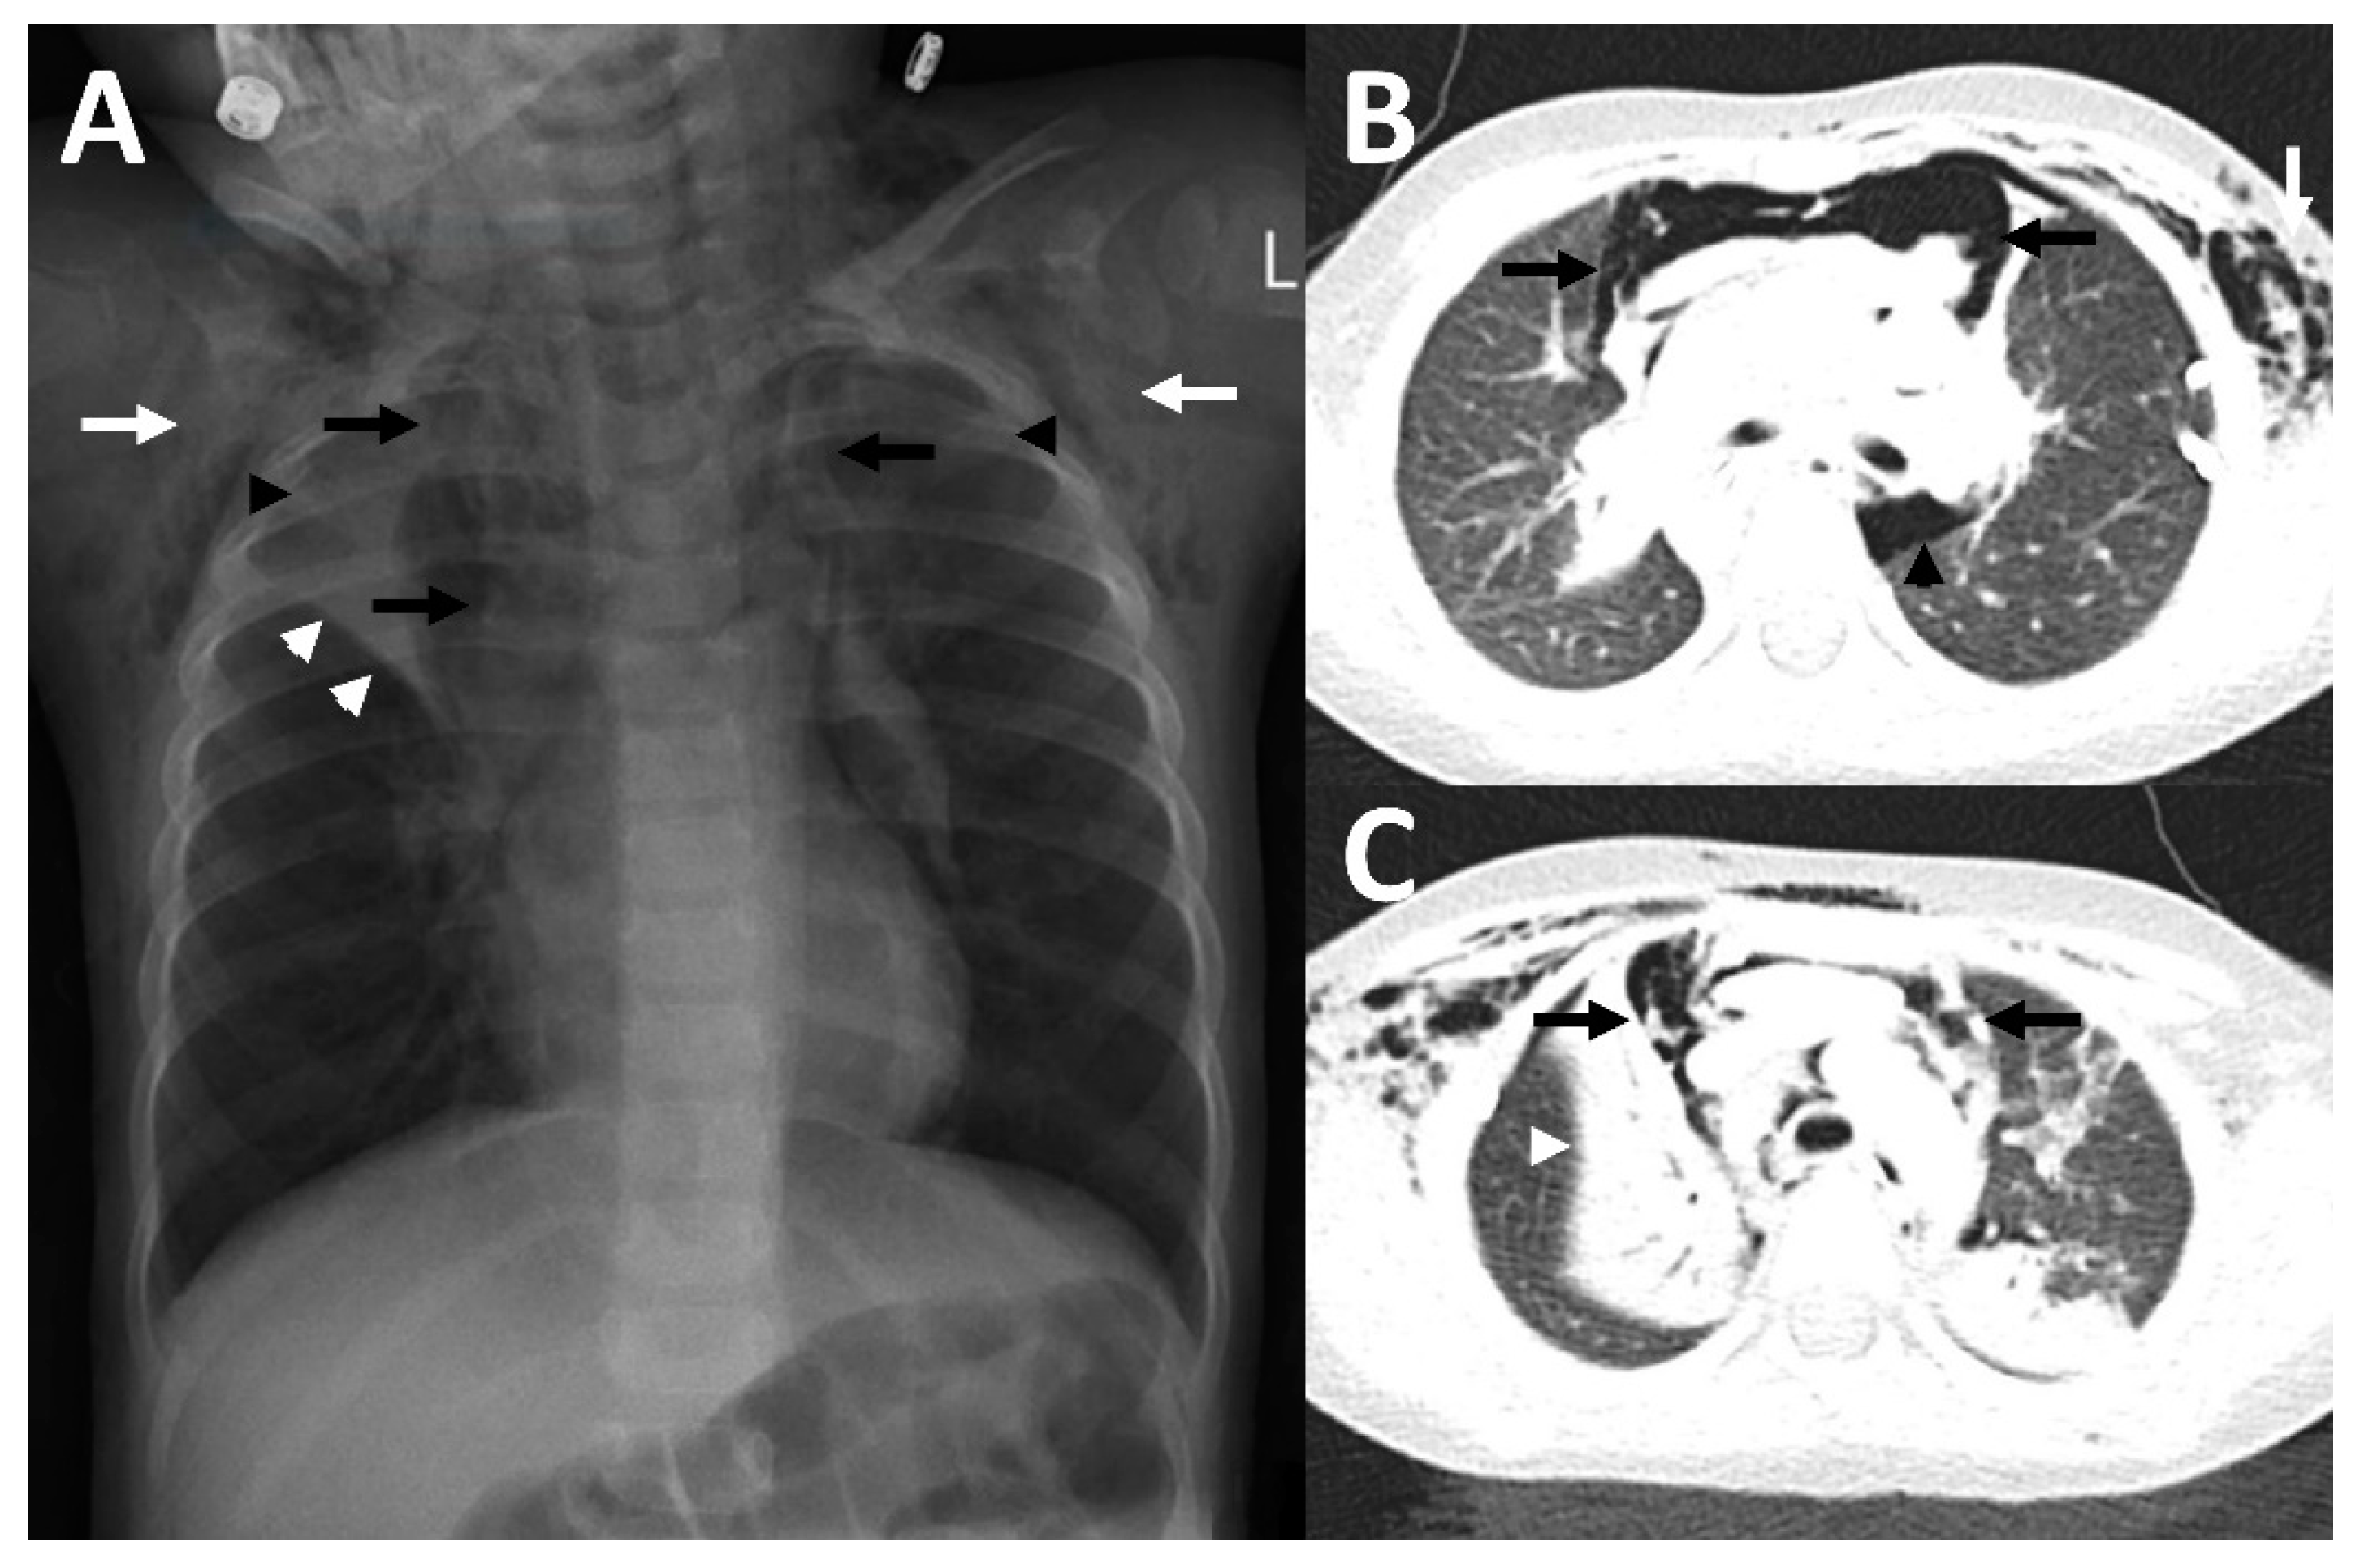

Figure 2.

Imaging findings in patient 2. In the chest x-ray (A), as well as in CT-imaging (B,C) bilateral subcutaneous emphysema (white arrows) and a pneumomediastinum (black arrows) with a Spinnaker sail (angel wing) sign ((A), thymus lobes marked with black arrowheads) was detected. In addition, there were atelectases (white arrowheads), predominantly of the right upper lobe, as well as a pneumothorax (black arrowhead in (B)).